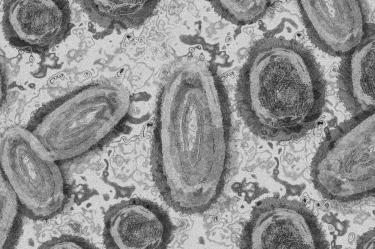

La viruela símica es una enfermedad viral que se presentó en el mundo desde hace tiempo; sin embargo, los primeros casos llegaron a México en mayo pasado.

El infectólogo del HU estableció que los síntomas son muy característicos e incluyen una erupción en la piel que por lo general son vesículas.